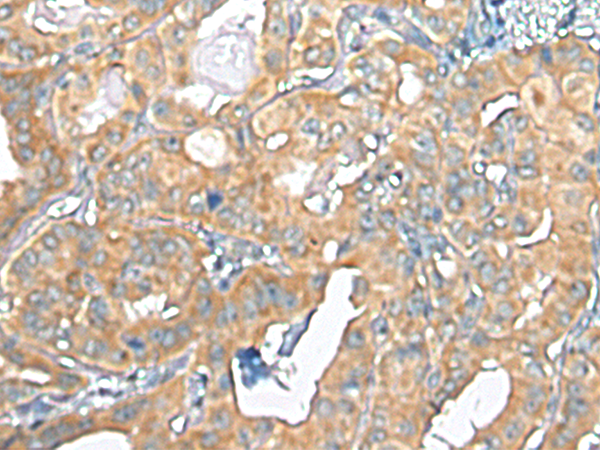

ELISA, IHC |

IHC positive control: |

Human thyroid cancer and Human liver cancer |

IHC Recommend dilution: |

25-100 |